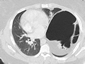

On physical exam she was obese (BMI 34) but in good general condition. There were no abnormalities on the thoracic and abdominal examination other than reduced breath sound at the left lung base. A chest x-ray showed substantial elevation of the left hemidiaphragm (Figure 1). A chest CT showed a massively distended left colon under the left diaphragm (Figure 2). A “sniff test” (fluoroscopic assessment of diaphragmatic function) showed paradoxical motion of the elevated hemidiaphragm.